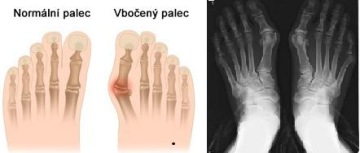

Hallux valgus - vbočený palec

Hallux valgus neboli vbočený palec – je deformita přednoží, která způsobuje změnu osy palce. Ten se špičkou dostává zevně od osy těla a přiklání se k druhému prstu. Na vnitřní straně, v místě základního kloubu palce pak vznikne typická boule, postupně se přidává bolest.